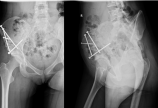

【髋关节】保髋手术复杂病例介绍(一)

病情概述:   患者,女性,23岁,左下肢跛行20余年。  骨盆X线片显示:左髋关节高位脱位。  下肢全长片显示:左下肢相对短缩。  髋造影MR片显示:左股骨头软骨质量欠佳。 [详情]